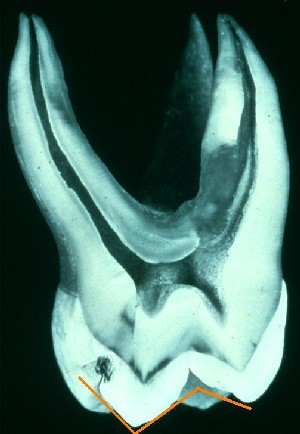

Tandslid under naturlige forhold. Når tænder udsættes for grov kost over lang tid vil emaljen blive slidt. Når emaljen regelmæssigt udsættes for slid vil plakken aldrig kunne blive cariesfremkaldende, fordi den hele tiden skal starte forfra. Moderne kost slider kun meget lidt på tænderne. Med regelmæssig plakfjernelse er det muligt at bevare et sygdomsfrit tandsæt med kun få slidskader gennem hele livet. Glatte tandoverflader gør det lettere at undgå sygdom på de flader hvor det naturlige slid er begrænset.

Emaljen dækker tandkronen og er karakteriseret ved at være kroppens hårdeste og mest slidresistente materiale. Emalje indeholder ikke levende celler og den påvirkes normalt ikke af kemi. Det er kun når bakterier får lov til at ophobes på overfladen eller den udsættes for syre i større mængder at emalje kan opløses. Emaljens tykkelse og overfladens form viser også at det er de mekaniske kræfter, der altid har haft afgørende betydning for tandsundhed. Tyggeflader har ved frembrud en meget ujævn overflade, som ved naturligt slid hurtigt udjævnes. Alle andre overflader er glatte, fordi man under almindelige forhold lettere kan holde en glat overflade bakteriefri. Det slid der gjorde at plakken med regelmæssige mellemrum blev fjernet fra tandoverfladerne medførte samtidig at nabotænder gnubbede og sled mod hinanden. Dette slid var årsagen til at der i 18-års-alderen også var plads til visdomstænderne i tandrækken. Udviklingen har altså gjort det helt klart at plak er uønsket på tandoverflader. I det hele taget har de mekaniske påvirkninger langt større betydning for at opretholde balancen i mundhulen. Man kan blot prøve at gnide en belagt tungeryg mod ganen. På den måde får man både ryddet lidt op i bakterierne på tungeryggen og i ganen.